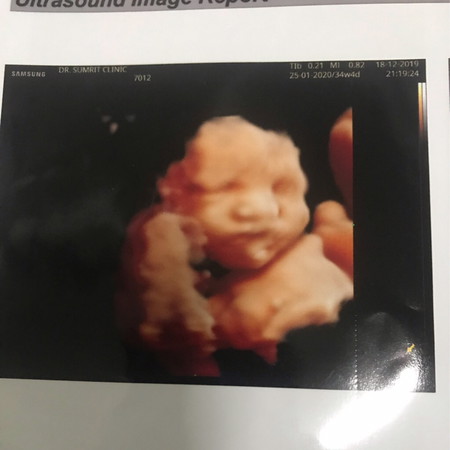

ซาวน์ 4มิติ

32วีค เพิ่งไปซาวน์4มิติมาค่ะ อยากดูรูป ตัวเล็กของแม่ๆ และอยากรู้ ว่า น้องจะออกมาเหมือนกับในรูปมั้ยคะ??

เราว่าสัก 70 % นะ 555+ แต่ละบ้านไม่น่าจะเหมือนกันจ้า

เหมือนเป๊ะเลยค่ะแม่ บ้านนี้ไปซาวน์ตอน33wk. ค่ะ